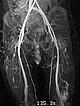

In der koronaren, T2-gewichteten, fettunterdrückten MRT im 32. Lebensmonat findet sich das charakteristische, stark hyperintense = weiße Signal einer Slow-flow-Gefäßmalformation in der labialen Läsion. Zudem auch ähnlich stark hyperintenses Signal in einer intramuskulären Läsion im Musculus vastus lateralis des linken Oberschenkels. Damit ist eine Gefäßmalformation sehr wahrscheinlich.